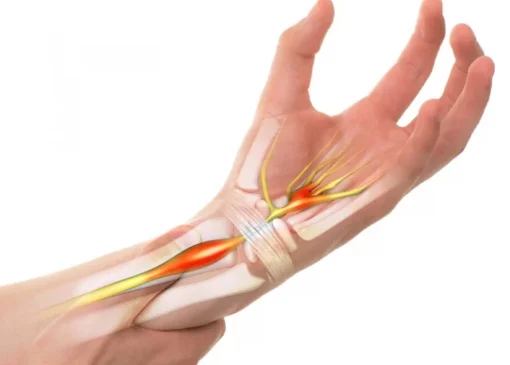

عصب سیاتیک طولانی ترین عصب بدن است که موجب ایجاد حس و کنترل پاها و اندام تهتانی بدن می شود. مادامی که این عصب تحریک شده، دچار التهاب می شود و در نتیجه موجب ایجاد درد در لگن و پاها خواهد شد. درد سیاتیک معمولا شدید و تیز است و در هنگام بلند شدن، نشستن و حتی حرکت زانوها منجر به درد بیشتر در لگن می شود. التهاب عصب سیاتیک در اثر عواملی مانند آرتروز ستون فقرات، دیسک کمر و تنگی کانال نخاعی ایجاد خواهد شد. یکی از عمده ترین دردها در ناحیه لگن به خاطر سیاتیک است. بنابراین می توان قرص های التیام دهنده سیاتیک را نیز به عنوان قرص برای درد استخوان لگن در نظر گرفت.